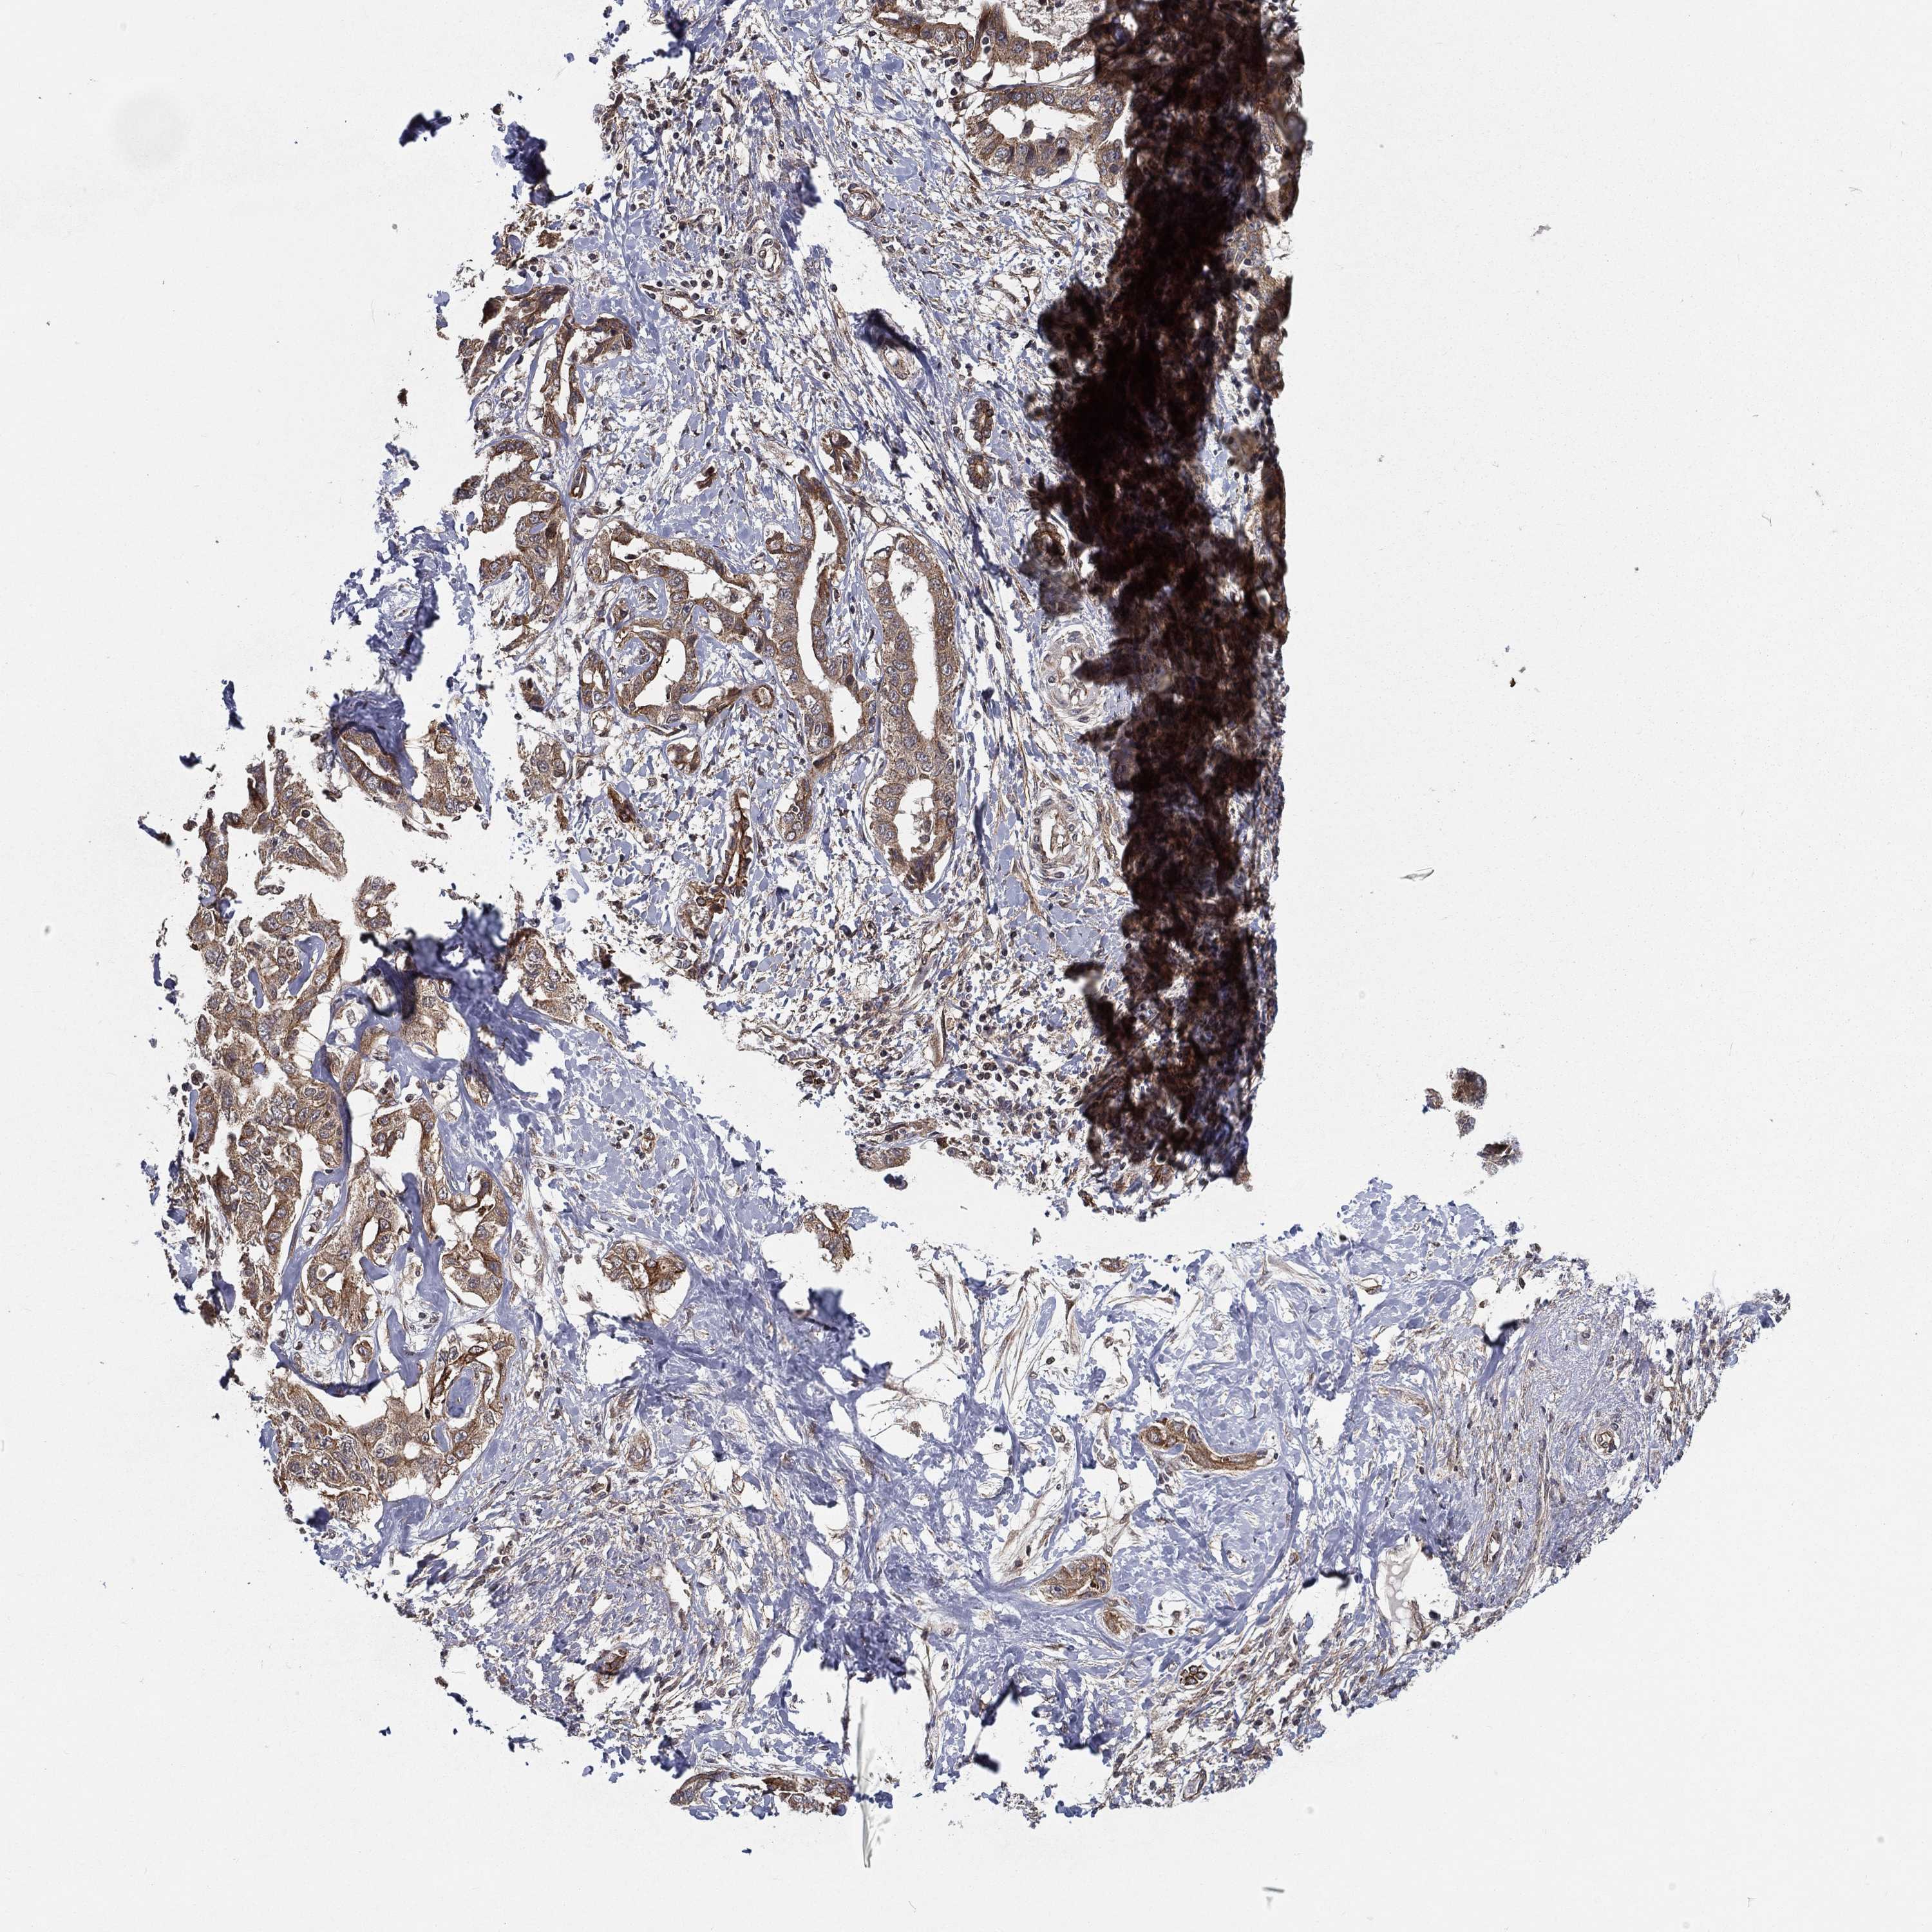

LIVER CANCER - Protein expressioni

A mouse-over function shows sample information and annotation data. Click on an image to view it in a full screen mode. Samples can be filtered based on level of antibody staining by selecting one or several of the following categories: high, medium, low and not detected. The assay and annotation is described here.

Note that samples used for immunohistochemistry by the Human Protein Atlas do not correspond to samples in the TCGA dataset.

Antibody stainingi

Antibody staining in the annotated cell types in the current human tissue is reported as not detected, low, medium, or high, based on conventional immunohistochemistry profiling in selected tissues. This score is based on the combination of the staining intensity and fraction of stained cells.

Each image is clickable and will lead to virtual microscopy that enables deeper exploration of all samples and also displays staining intensity scores, fraction scores and subcellular localization as well as patient and tissue information for each sample.

Antibody HPA041412

Antibody HPA056006

Staining

High

Medium

Low

Not detected

Intensity

Strong

Moderate

Weak

Negative

Quantity

>75%

75%-25%

<25%

None

Location

Nuclear

Cytoplasmic/membranous

Cytoplasmic/membranous,nuclear

Cholangiocarcinoma

Carcinoma, Hepatocellular, NOS